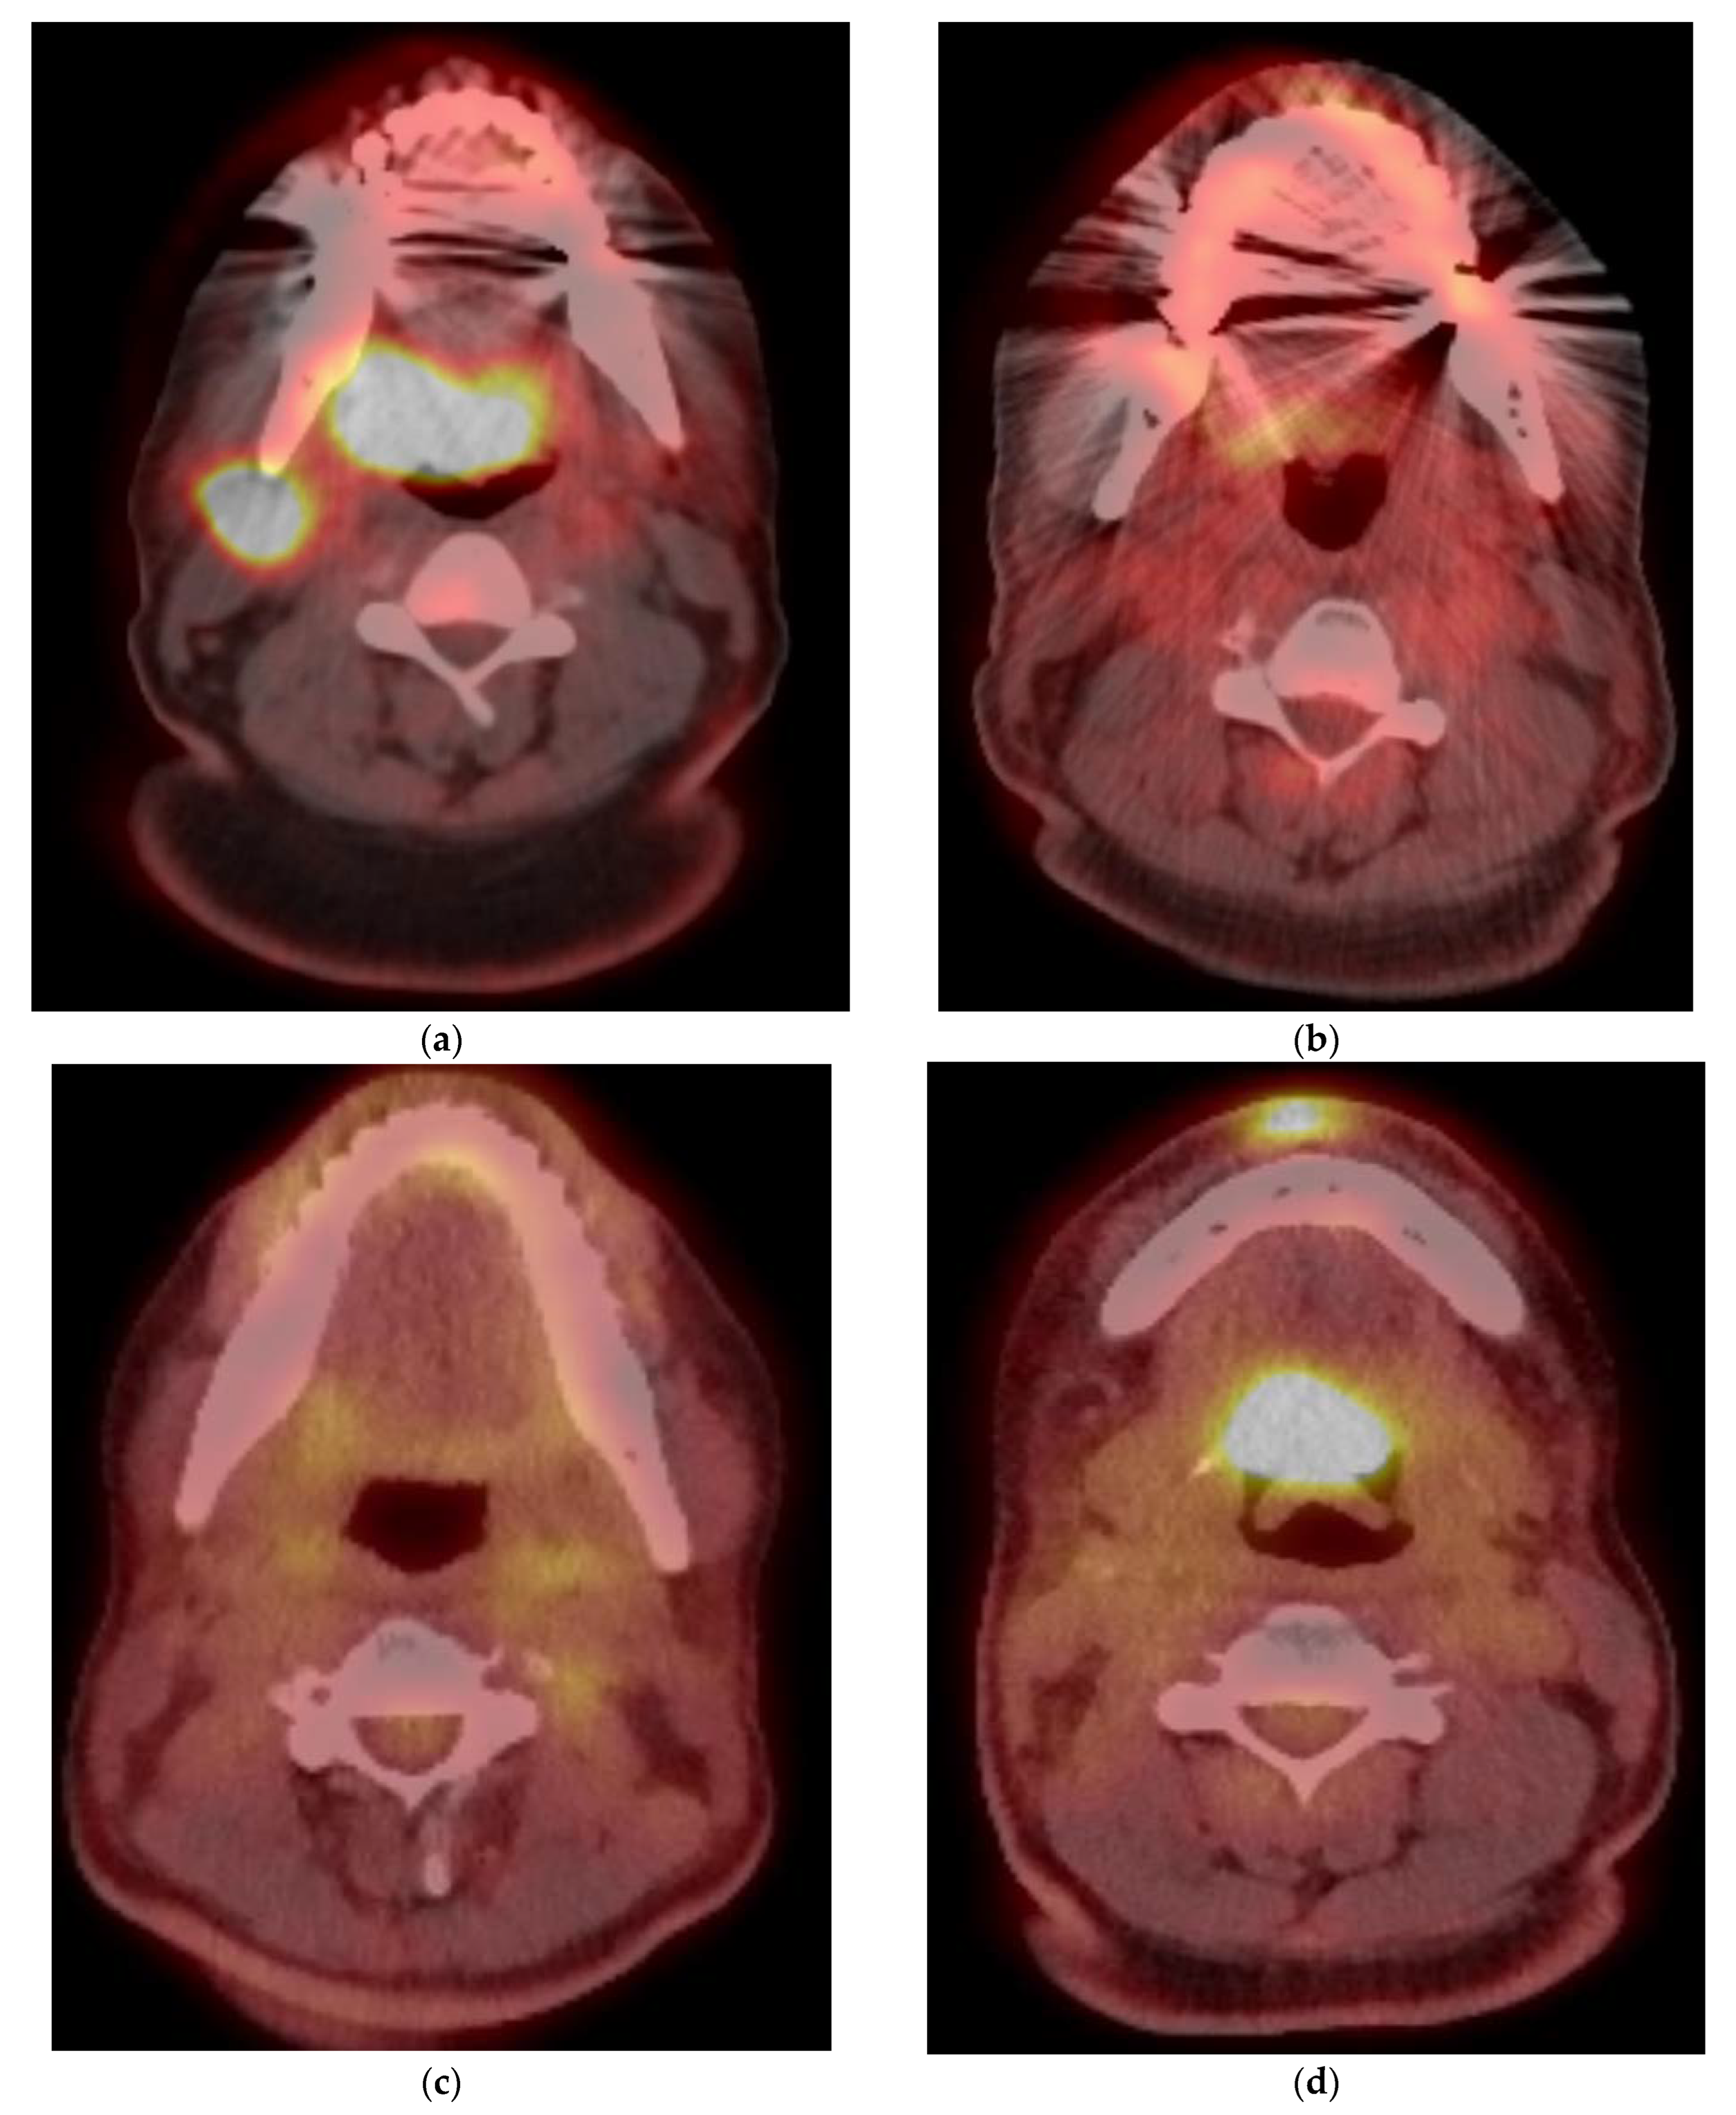

5. Imaging of Oropharyngeal Cancers

8.1. Initial Staging